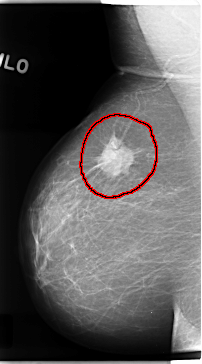

FILE: C_0121_1.RIGHT_MLO.OVERLAY

TOTAL_ABNORMALITIES 1

ABNORMALITY 1

LESION_TYPE MASS SHAPE IRREGULAR MARGINS SPICULATED

ASSESSMENT 5

SUBTLETY 5

PATHOLOGY MALIGNANT

TOTAL_OUTLINES 1

BOUNDARY